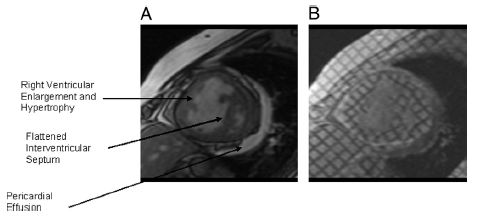

MR

心脏核磁共振测量的右心功能指标包括:RV收缩/舒张末期容积,RV射血分数、室壁厚度、心肌质量、心肌质量指数等。

右心衰:右室大,左室小,左室呈D形,少量心包积液